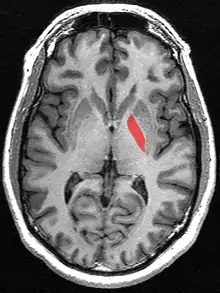

يتم وضع وتثبيت اطار التوضيع التجسيمي (بالانجليزية: stereotactic frame) على رأس المريض تحت التخدير الموضعي، وقد يستخدم المنوم أو المخدر العام للتركيب إذا كانت ارتعاشات المريض شديدة تمنع من القدرة على تركيب الإطار. يتم تصوير رأس المريض بالرنين المغناطيسي لتكوين صورة مجسمة ثلاثية الأبعاد لتحديد موقع الهدف (الكرة الشاحبة الداخلية)، في حال وجود مانع لاستخدام الرنين المغناطيسي يتم اجراء صورة مقطعية للرأس.

عند التأكد من وجود الإبرة بالمكان الصحيح يتم كي الجهة الخلفية البطنية من الكرة الشاحبة الداخلية بابرة قطرها 1.1 مليمتر وطرف عار 3 مليمتر. يتم عمل كي مؤقت بدرجة حرارة 42 درجة مئوية، وإذا لم يكن هنالك أي مضاعفات جانبية يتم الكي بشكل دائم بدرجة حرارة بين 75 إلى 80 درجة مئوية لمدة 60 ثانية. يتم سحب الإبرة للأعلى 2الى3 مليميتر مع كي لمدة 60 ثانية. في بعض الأحيان يتم تحريك الإبرة للكي أيضاً إلى الامام 2 مليمتر وأيضاً باتجاه منتصف الرأس 2 مليميتر، وهذا يعتمد على حجم الكرة الشاحبة الداخلية. عند الانتهاء يتم سحب الإبرة بعد أن تبرد لدرجة حرارة 42 درجة مئوية أو أقل، ومن ثم خياطة جرح جلدة الرأس.